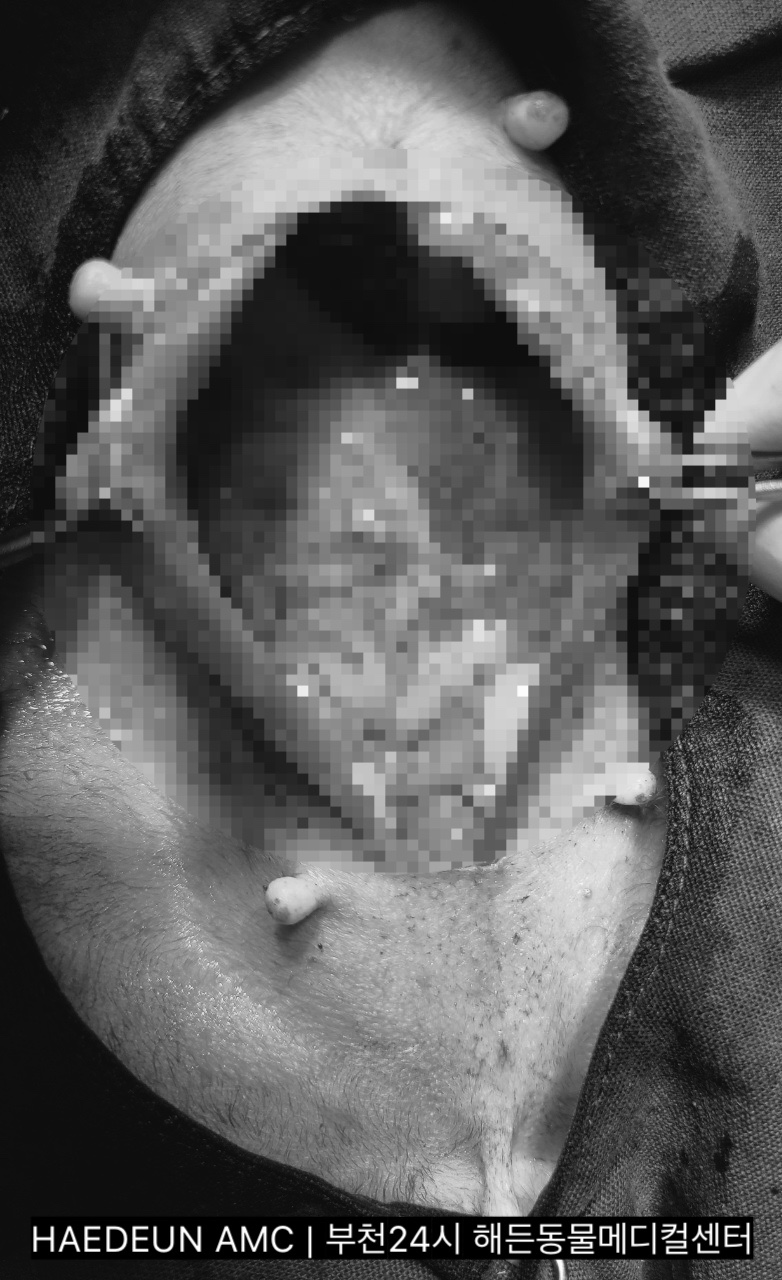

수술 시작 후 얼마 되지 않아 적출된 B**의 자궁입니다

자궁 내/외부로 종양 덩어리가 확인됩니다.자궁 내부에는 고름이 확인되었습니다.

적출된 아이의 종양이나 난소 등 내부 생식기의 모습입니다.